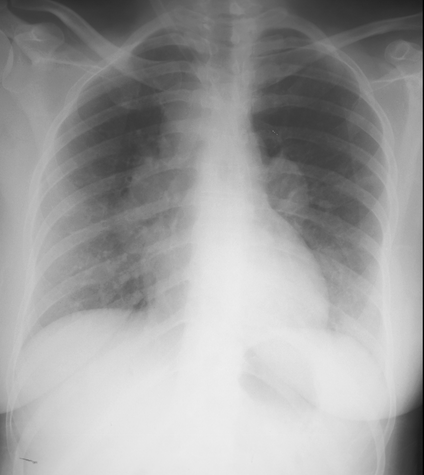

R) heart failure